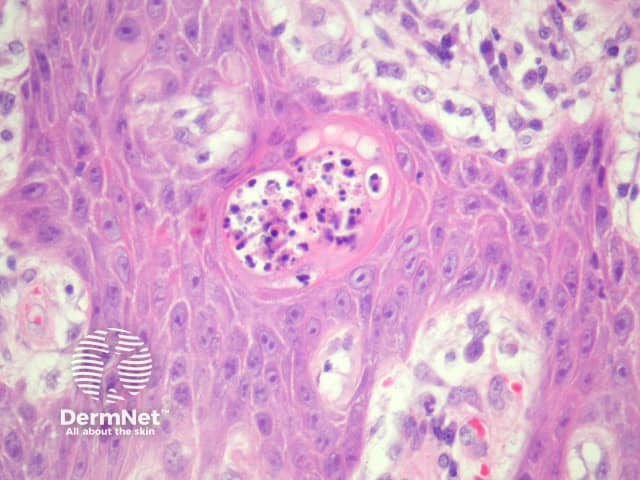

In blastomycosis-like pyoderma, sections usually show a broad verrucous lesion with epidermal papillomatosis which may resemble a keratoacanthoma (figure 1). There may be surface erosion and suppuration (figure 2). Numerous cystic spaces connect with the surface via draining sinuses (figure 3). There may be a pseudo-infiltrative growth pattern as the regenerative epithelium mimics an invasive squamous cell carcinoma (figure 4). Neutrophilic collections are present in the dermis and within squamous islands (figures 5, 6).

Figure 4

Figure 5